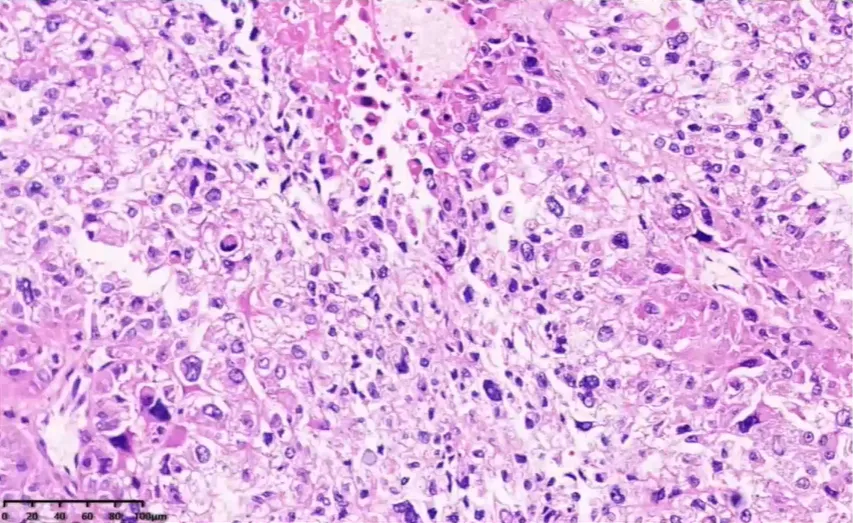

病例2

手术所见(2024.8.8):右侧髂窝处巨大肿物约 10×9cm,灰白质硬,布满怒张血管,沿腹主动脉右后壁多发肿大淋巴结,较大者直径 3cm,且融合成团。

胞浆嗜酸或透亮,细胞异型性大,可见瘤巨细胞。

肿瘤性坏死

脉管内瘤栓

网状纤维染色。网状纤维结构破坏。厚壁不均。

🌺 病理诊断:肾上腺皮质癌。